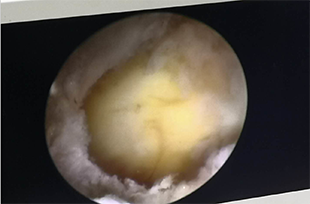

為迅速緩解患者癥狀,根據患者病情并結合影像學診斷,習超杰院長、非手術治療毛珺珺主任為患者制定了目前醫院最新微創手術方案UBE技術下經皮穿刺頸腰椎間盤切除術”。并為林先生家屬說明手術情況后,92620:00習超杰院長、非手術治療毛珺珺主任團隊的共同努力下,在透視下將UBE內鏡放入到腰椎間盤脫出部位,使用UBE專用器械靶精確定位,將神經根和硬膜囊牽向內側并保護起來后,精確摘除突出椎間盤,術中出血少約100ml,沒有出現其他異樣,23:30林先生手術非常成功,術后僅留下21厘米小切口,麻醉過后也并無異常。

UBE是脊柱微創技術,適用于頸椎、胸椎、腰椎的退行性病變。與椎間孔鏡的單通道不同,該技術通常建立兩個通道,一個為觀察通道,一個器械操作通道。觀察通道一般會用到0°或30°UBE內鏡,操作通道可以應用常規的脊柱外科及運動醫學的器械如刮匙、磨鉆、UBE刨刀、UBE射頻消融電極、椎板咬骨鉗、髓核鉗、神經拉鉤等。當然有專門的器械包,甚至可以通過UBE技術完成鏡下融合手術。

4、水介質中操作,視野更加清晰,特殊器械可保持順暢出水;